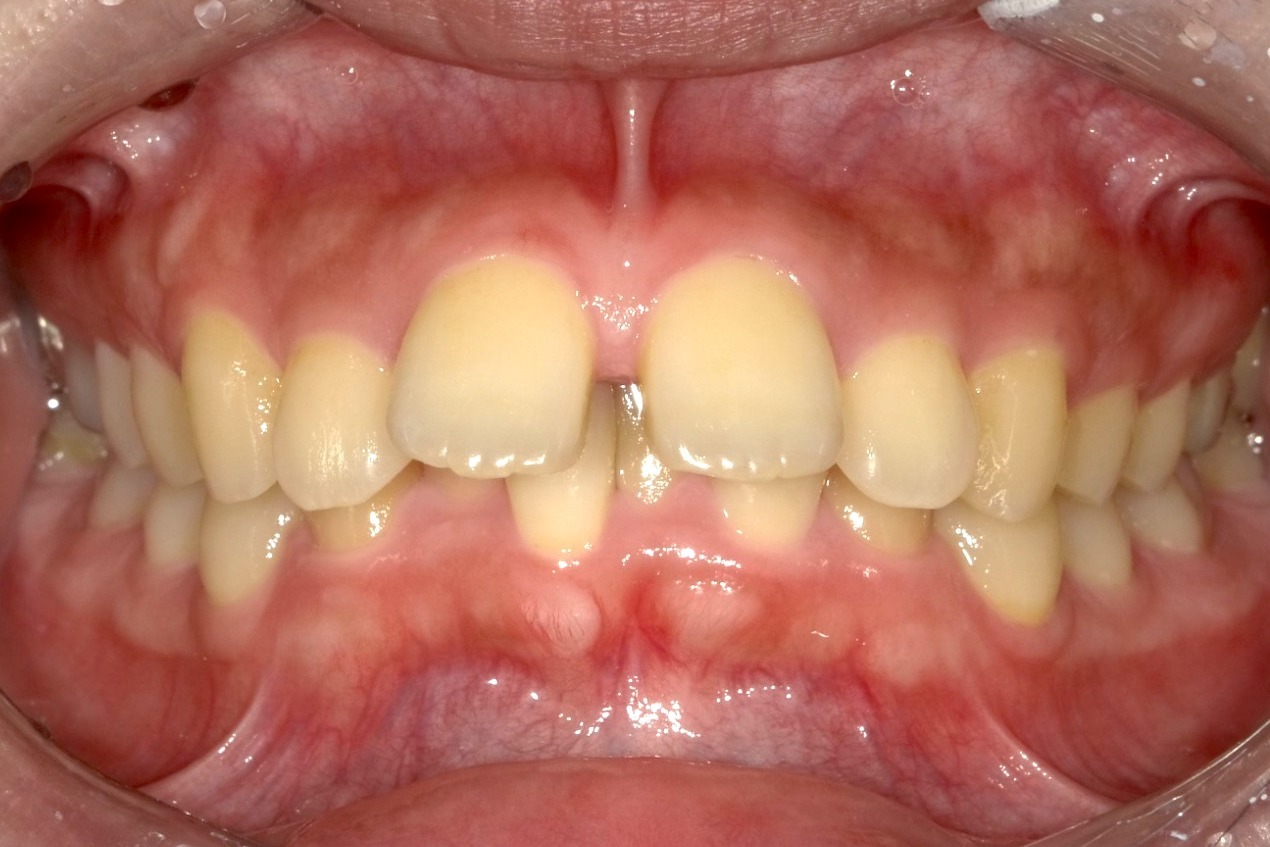

マウスピース矯正の失敗例

歯を並べるスペースの確保のために歯を削りすぎた結果、歯並びが完全に治らず前歯がすきっ歯になっています。

当院には、他院でマウスピース矯正を受けたものの、思うような結果が得られなかった患者さまが数多く来院されます。

この患者さまはインビザラインを4年間続けたものの、不十分な診断と治療計画によって歯を削りすぎてしまい、歯並びも咬み合わせも整わなかったケースです。